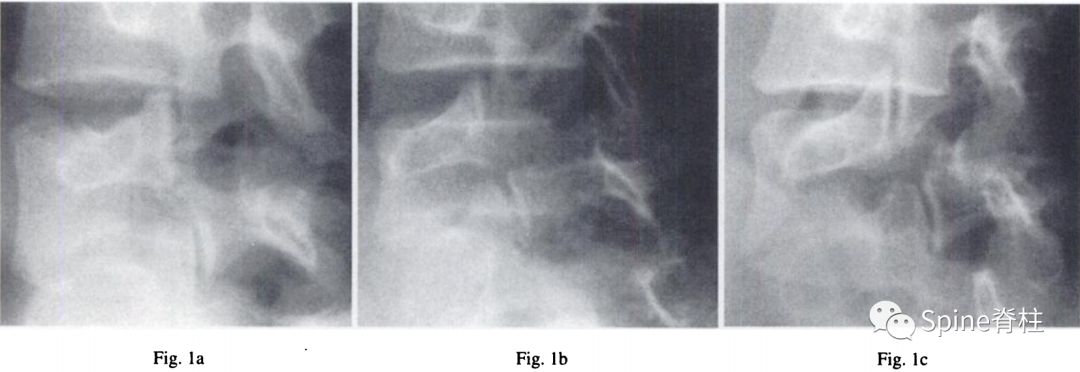

1. 峡部裂的Morita分型

- 早期 (early):可见峡部骨折线

- 进展期 (progressive):骨折断端间隙增宽

- 终末期 (terminal): 假关节形成

图:早期(a),进展期(b),终末期(c)

随后,Sairyo教授进一步CT研究,将Morita分型早期又分为 最早期 (very early): 骨折线模糊或不连续的骨折线和 晚早期 (late-early): 骨折线清晰明显。

图:腰5双侧峡部裂,右侧为 最早期 ,左侧为 晚早期